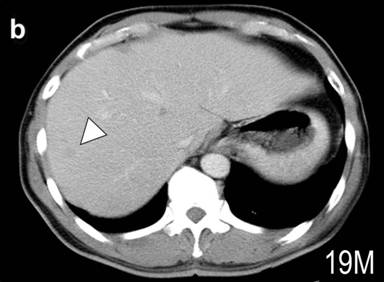

Figure 1. CT scan image of the abdomen. a. Large tumor was found at the tail of the pancreas (arrow heads). The CT scan of the liver 19 months (b.) and 25 months (c.) after the operation. Arrowheads indicate one of the metastatic tumors. The size appeared unchanged at 25 months. |

After the operation, VIP and calcitonin levels were decreased to 44 and 553 pg/mL, respectively, and diarrhea disappeared. Twelve months after the operation, however, the calcitonin level was gradually increased, and 19 months it reached at 3,980 pg/mL. CT demonstrated several small metastatic tumors in the liver (Figure 1b). Treatment with intramuscular injection of long-acting octreotide at a dose of 20 mg/month was started. Twenty-five months, the calcitonin was reduced to 803 pg/mL, and the patient has no endocrine symptom. The sizes of metastatic tumors in the liver appear unchanged (Figure 1c).